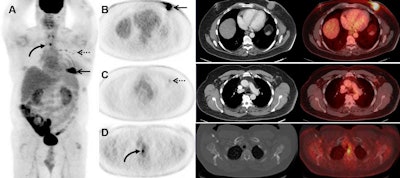

The images revealed previously unsuspected distant metastases in seven patients (18%), whose conditions were upgraded to stage IV breast cancer. The change in staging included three (16%) of 19 initial stage IIB patients and four (33%) of 12 initial stage III patients.

The researchers also observed suspected metastatic sites in the bone of six patients (15%) and in the lungs of three men (7%), and there were distant nodal metastases in three subjects (7%).